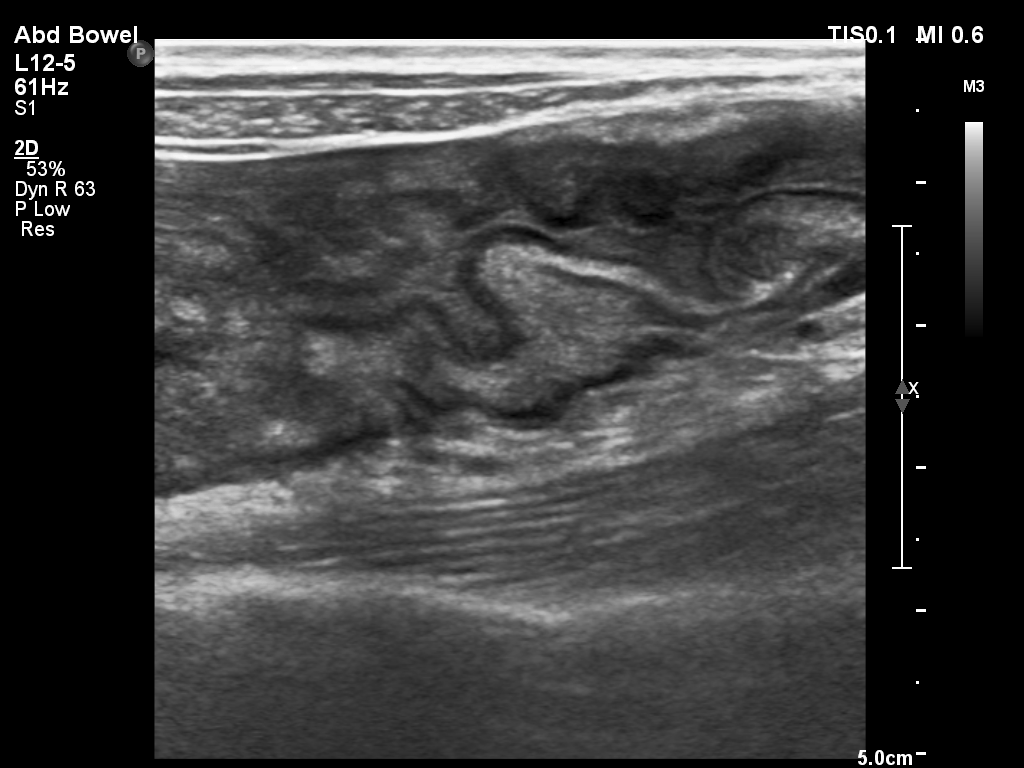

结肠超声

结肠超声是应用高频线振探头扫查炎性肠病患者的病变肠管,对病变范围、增厚程度、狭窄情况、炎症阶段进行评估与诊断。

虽然肠道超声检查因为设备检查原理的限制,具有可视区域范围小、缺少全景视角的不足,但超声检查也同时具有费用低、设备易获得、无辐射、可实时评估肠蠕动、空间分辨率高、不需要镇静、麻醉或抗蠕动药物、不需要口服或静脉注射造影剂等优势。

超声检查能实时观察肠壁的增厚、充血、管腔异常和蠕动改变;肠周系膜组织的炎性改变、纤维脂肪增生、局部淋巴结增大、瘘管和瘘道的形成及异常积液及肛周病变。为临床诊断和治疗方案的制定提供支持,同时适用于炎性肠病患者的检查及治疗后的复查。